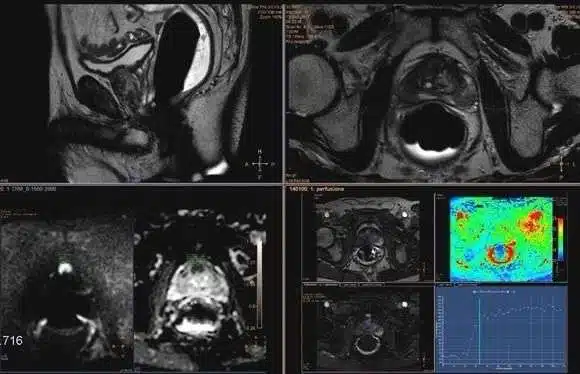

„În funcție de modificările observate de medicul radiolog pe imaginile RMN, leziunile vor fi stadializate folosind așa zisul scor PIRADS. Acesta poate avea o valoare de la 1-5, evaluând astfel riscul de malignitate. Și putem avea un PIRADS 1, ceea ce înseamnă fără modificări la nivelul prostatei, prezența neoplaziei fiind improbabilă, PIRADS 2 – modificări cu aspect de benignitate, prezența neoplaziei este foarte puțin probabilă, PIRADS 3 – prezența cancerului este echivocă, necesitând investigații suplimentare, PIRADS 4 – prezența cancerului este probabilă, necesitând investigații suplimentare, și PIRADS 5 – prezența cancerului foarte probabilă, necesitând investigații suplimentare”, adaugă asist. univ. Roxana Iacob.